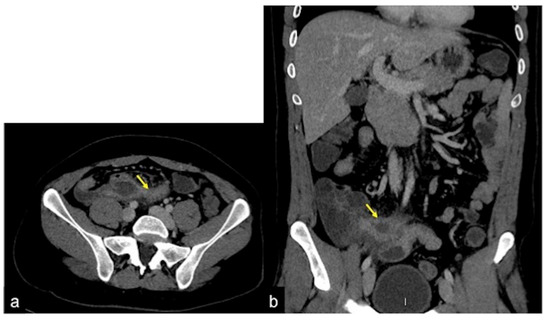

| Meckel’s Diverticulum (Figure 30) | Asymptomatic or, rarely, massive gastrointestinal bleeding. | A diverticulum with fluid or air content originating from the antimesenteric side of the distal ileum. |

| Aorto-Enteric Fistula (Figure 31) | Bleeding in a patient with a history of surgery for aortic aneurysm. | A connection between the aorta and the intestinal lumen. Absence of adipose cleavage planes. |